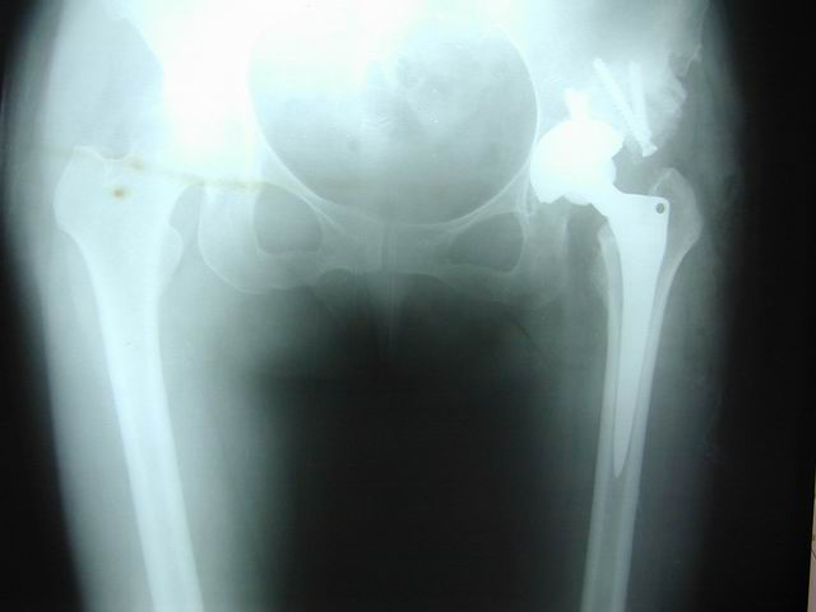

女性患者,48岁,右髋疼痛25年,加重1年

术后5天,脱位

切开复位

术后4月,再一次脱位

屋漏偏遭连夜雨